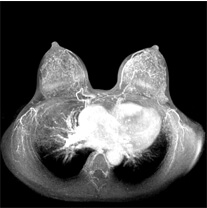

- MRI検査は、強い磁力を発生するMRI装置を用いて、乳房の病巣を画像化し、診断する検査です。

- MRI検査には、撮像条件を変えて画像のコントラストを調節でき、また、縦・横・斜めなど、任意の方向からの断層画像を得ることができるという利点があり、乳がん診療においてはマンモグラフィ検査や超音波検査よりも精度が高い「乳腺MRI」が有用と考えられています。